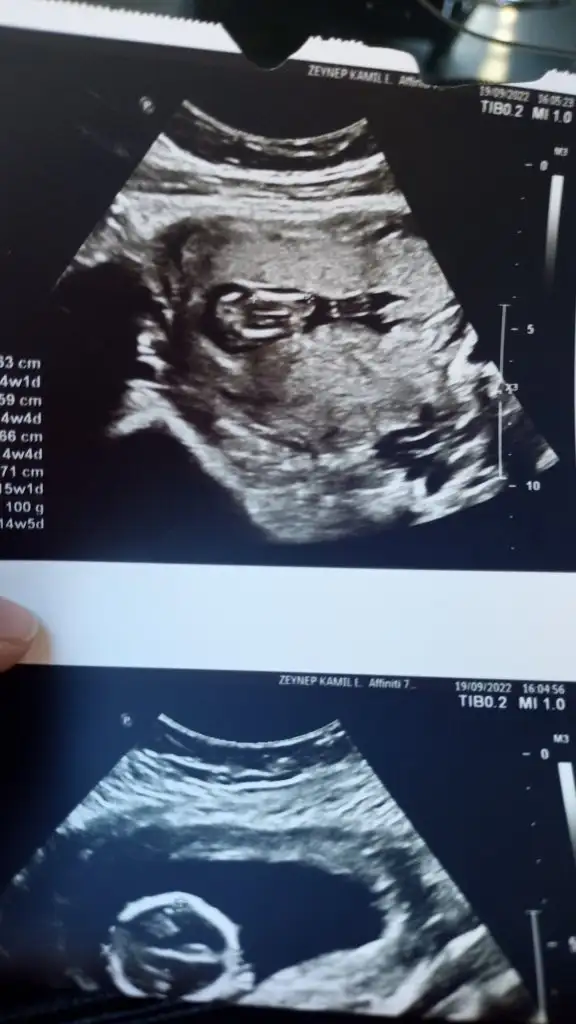

12 haftalık benimkini de yorumlar mısınızRamzi teorisine göre cinsiyet tahmini yapabilir misiniz?

Vajinal ultrasonla bakıldı 7+5 haftalıkŞimdiden teşekkürler